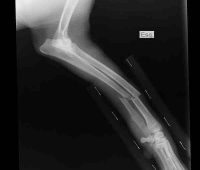

Remedios caseros por fractura del húmero

Remedios caseros por fractura del húmero Conoce todo sobre la fractura del húmero Cuando hay fractura en un brazo, el hueso roto es el húmero, o sea el hueso que une los huesos del antebrazo, cúbito y radio en el codo, con el hombro (clavícula y omoplato). En esta clase de fracturas hay hinchazón, deformación, dolor y generalmente hemorragia interna superficial.